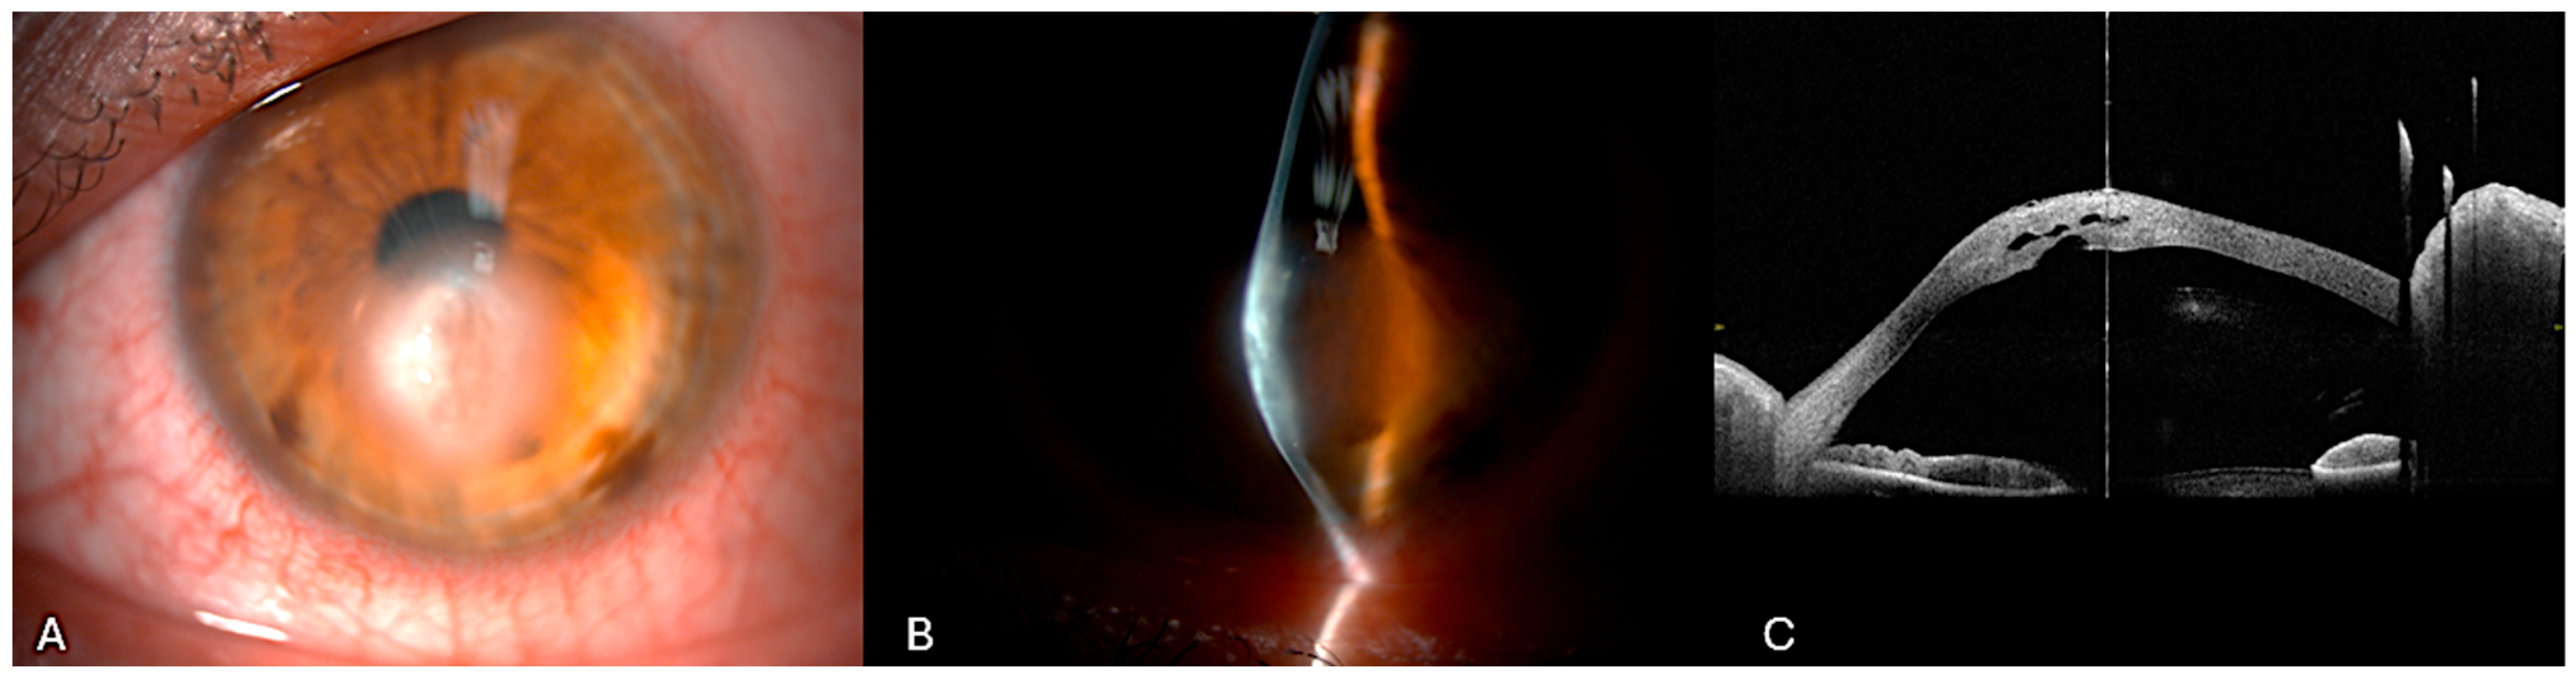

Case Highlight